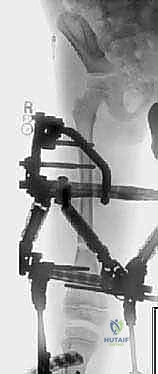

أولاً: جهاز إليزاروف الدائري (The Ilizarov Circular Fixator)

يُعد جهاز إليزاروف من أعظم الابتكارات في تاريخ جراحة العظام. يتكون الجهاز من حلقات معدنية تحيط بالطرف، متصلة ببعضها بواسطة قضبان ملولبة، ويتم تثبيتها في العظم باستخدام أسلاك معدنية دقيقة جداً (K-wires) مشدودة بقوة عالية.

مميزات جهاز إليزاروف:

* تصحيح ثلاثي الأبعاد: لا يقتصر دوره على التطويل فقط، بل يمكنه تصحيح التشوهات المعقدة (الاعوجاج، الدوران، والانزلاق) في نفس الوقت.

* الثبات الميكانيكي الفائق: يسمح للمريض بتحميل الوزن والمشي في وقت مبكر جداً بعد العملية، مما يحفز نمو العظم.

* الحفاظ على الأنسجة: الأسلاك الدقيقة تقلل من الأضرار التي تلحق بالعضلات والأنسجة الرخوة.